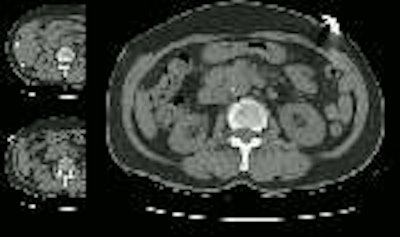

A contrast enhanced CT scan was then performed which demonstrated a Type A aortic dissection that severely compromised the true lumen of the ascending aorta. There was no perfusion to the right kidney which was being supplied via the false lumen: